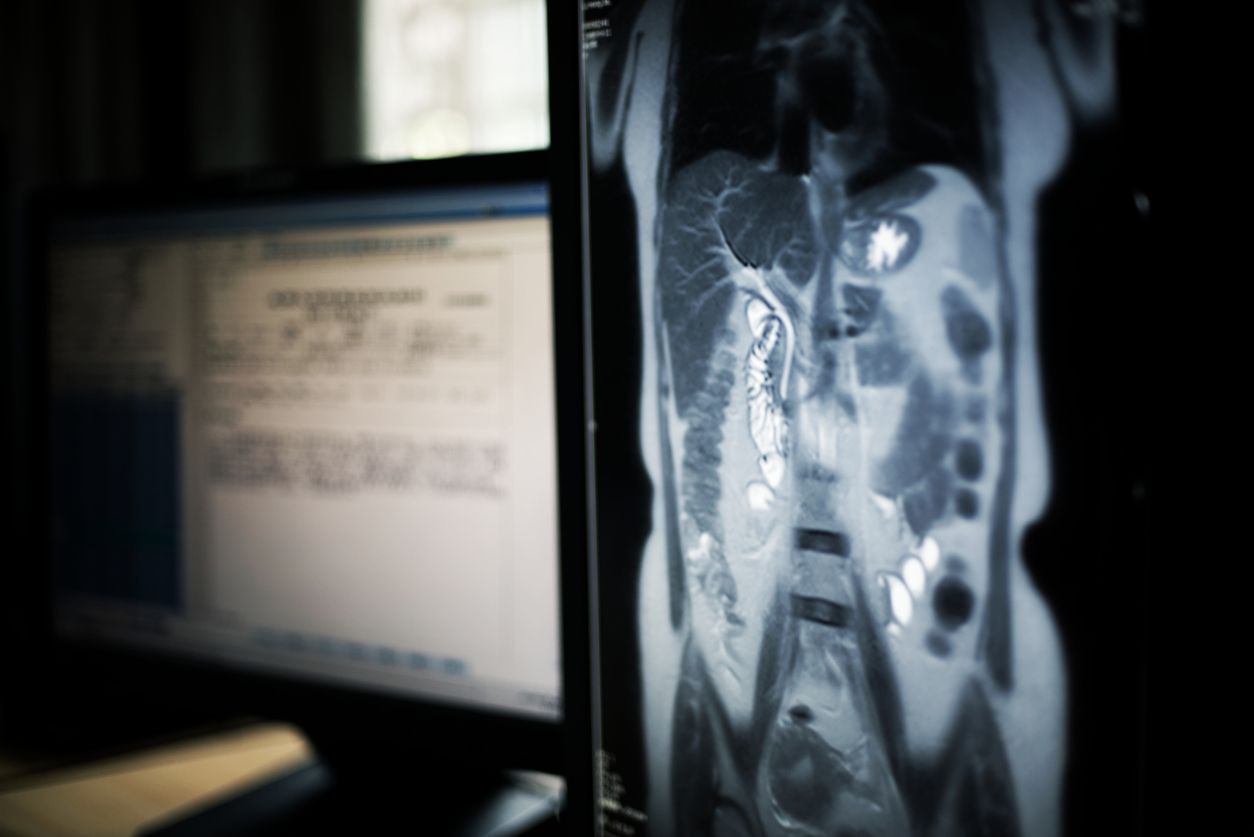

Ein Mann in Indien hat diesen Fakt offensichtlich falsch verstanden. Der 26-Jährige Bodybuilder wollte sein Training mittels Zinkzufuhr unterstützen, indem er wochenlang Münzen und Magnete schluckte. Nachdem er seit mehr als 20 Tagen über wiederholtes Erbrechen und Bauchschmerzen geklagt hatte, suchte er das Sir-Ganga-Ram-Krankenhaus in Delhi auf. Ein CT-Scan des Bauches zeigte eine riesige Ladung Münzen und Magnete, die zu einem Darmverschluss geführt hatten – ein lebensbedrohlicher Zustand. In einer Operation wurden ihm die Fremdkörper in Magen und Darm entfernt.